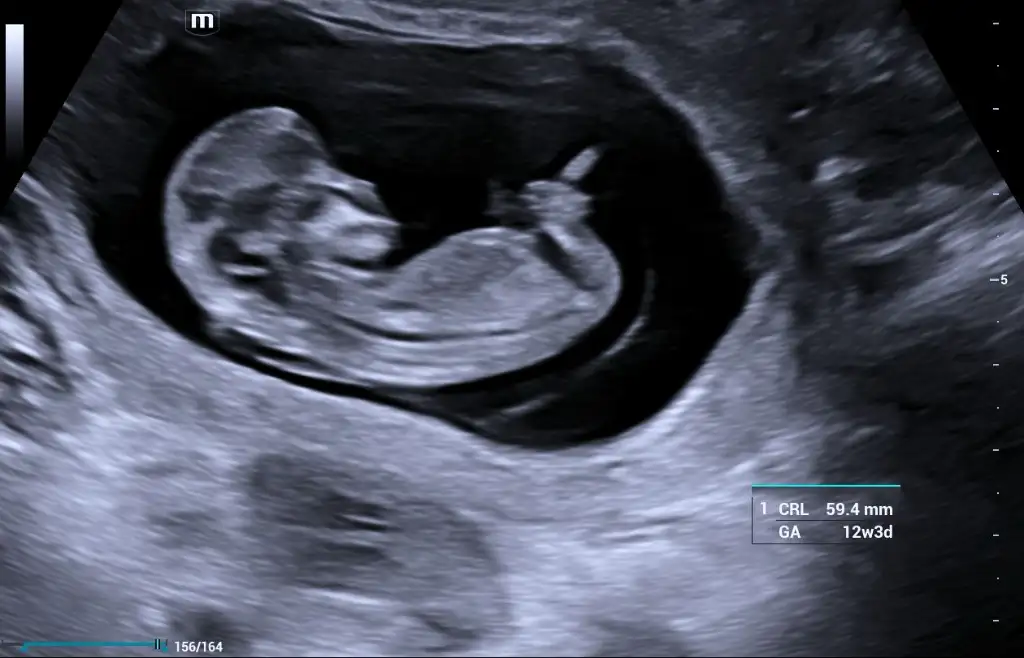

Aramizda bir gün var sizinle ama benim epey mide sorunlarım var. Bence hepimizinki kendine ozgu hic kendinize dert etmeyin❣Kızlar bazı günler ağır belirtiler yaşarken bazı günler sanki hamile değilmişim gibi oluyo bugün 9+1 olduk